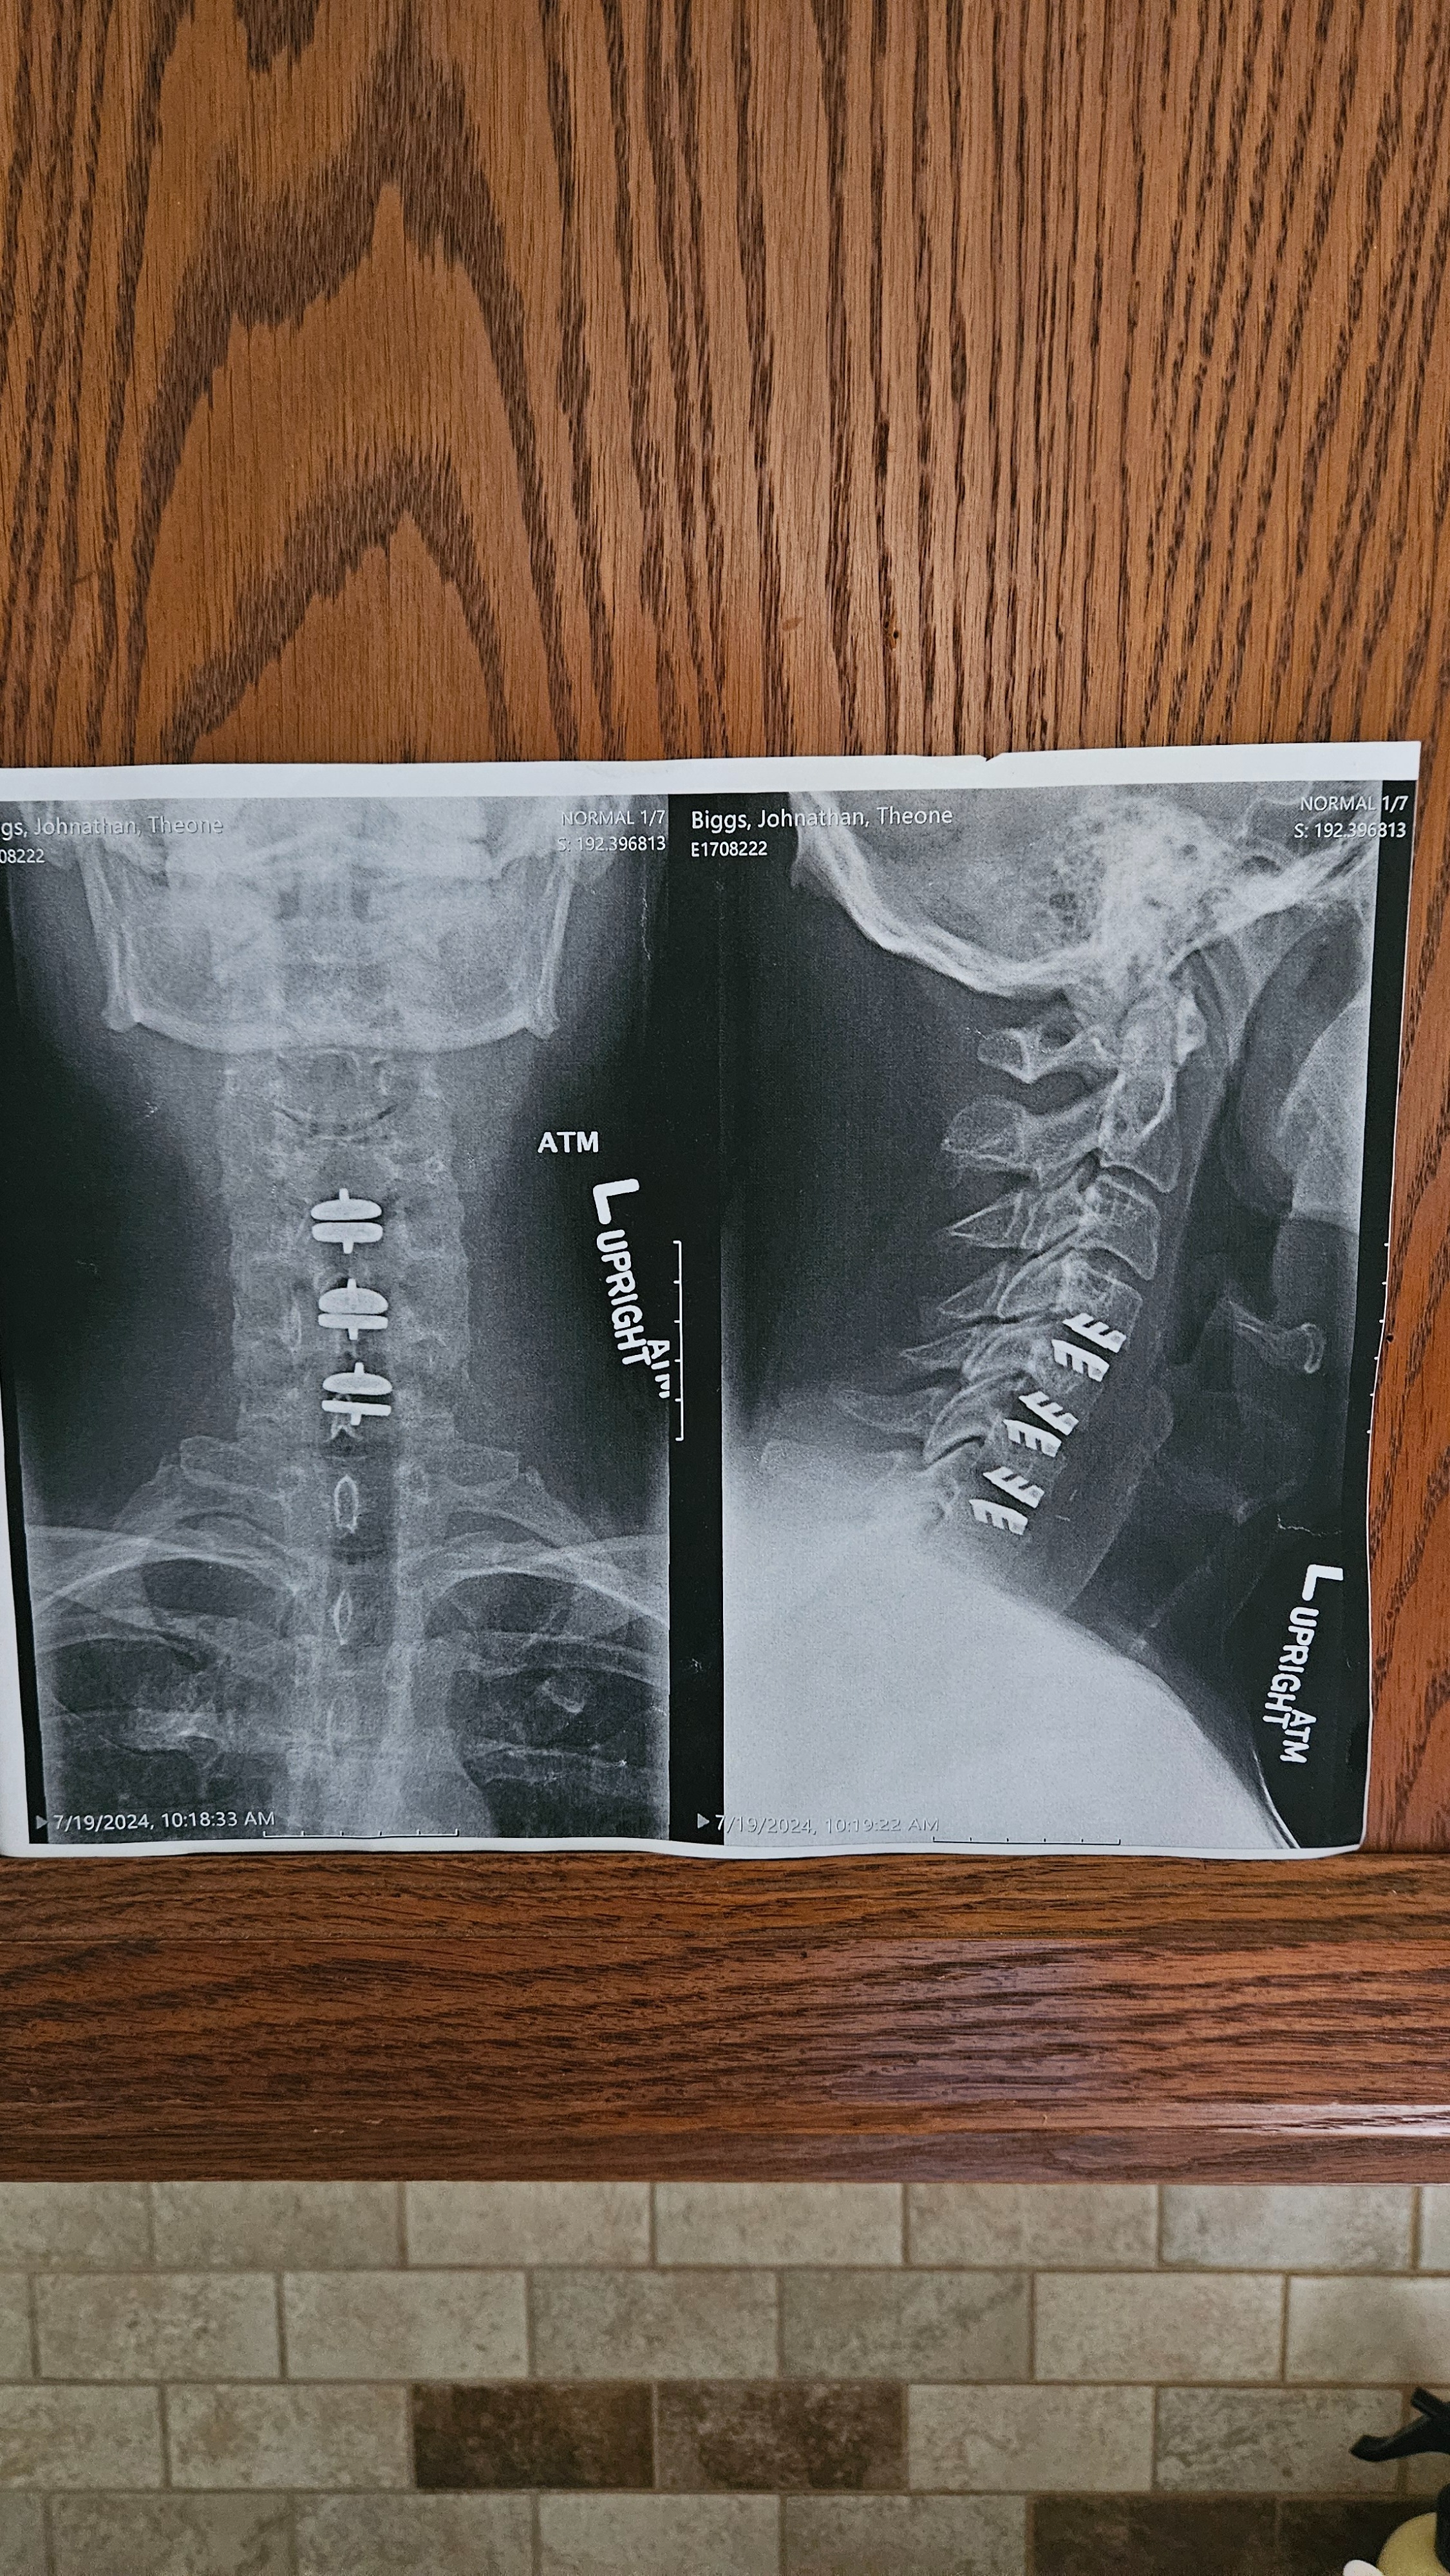

Hello, friends, family, and kind strangers. My name is John Biggs, and I'm reaching out from Fargo, North Dakota, with a heavy heart but hopeful spirit. For years, I've been battling severe back and neck issues that have turned my life upside down. What started as chronic pain from an injury escalated into a series of surgeries—I've undergone multiple procedures on my spine, including fusions and disc replacements, to try and regain some mobility and relief. Each surgery came with its own set of challenges: long recovery times, physical therapy, and mounting bills that I simply couldn't keep up with on my limited disability income.